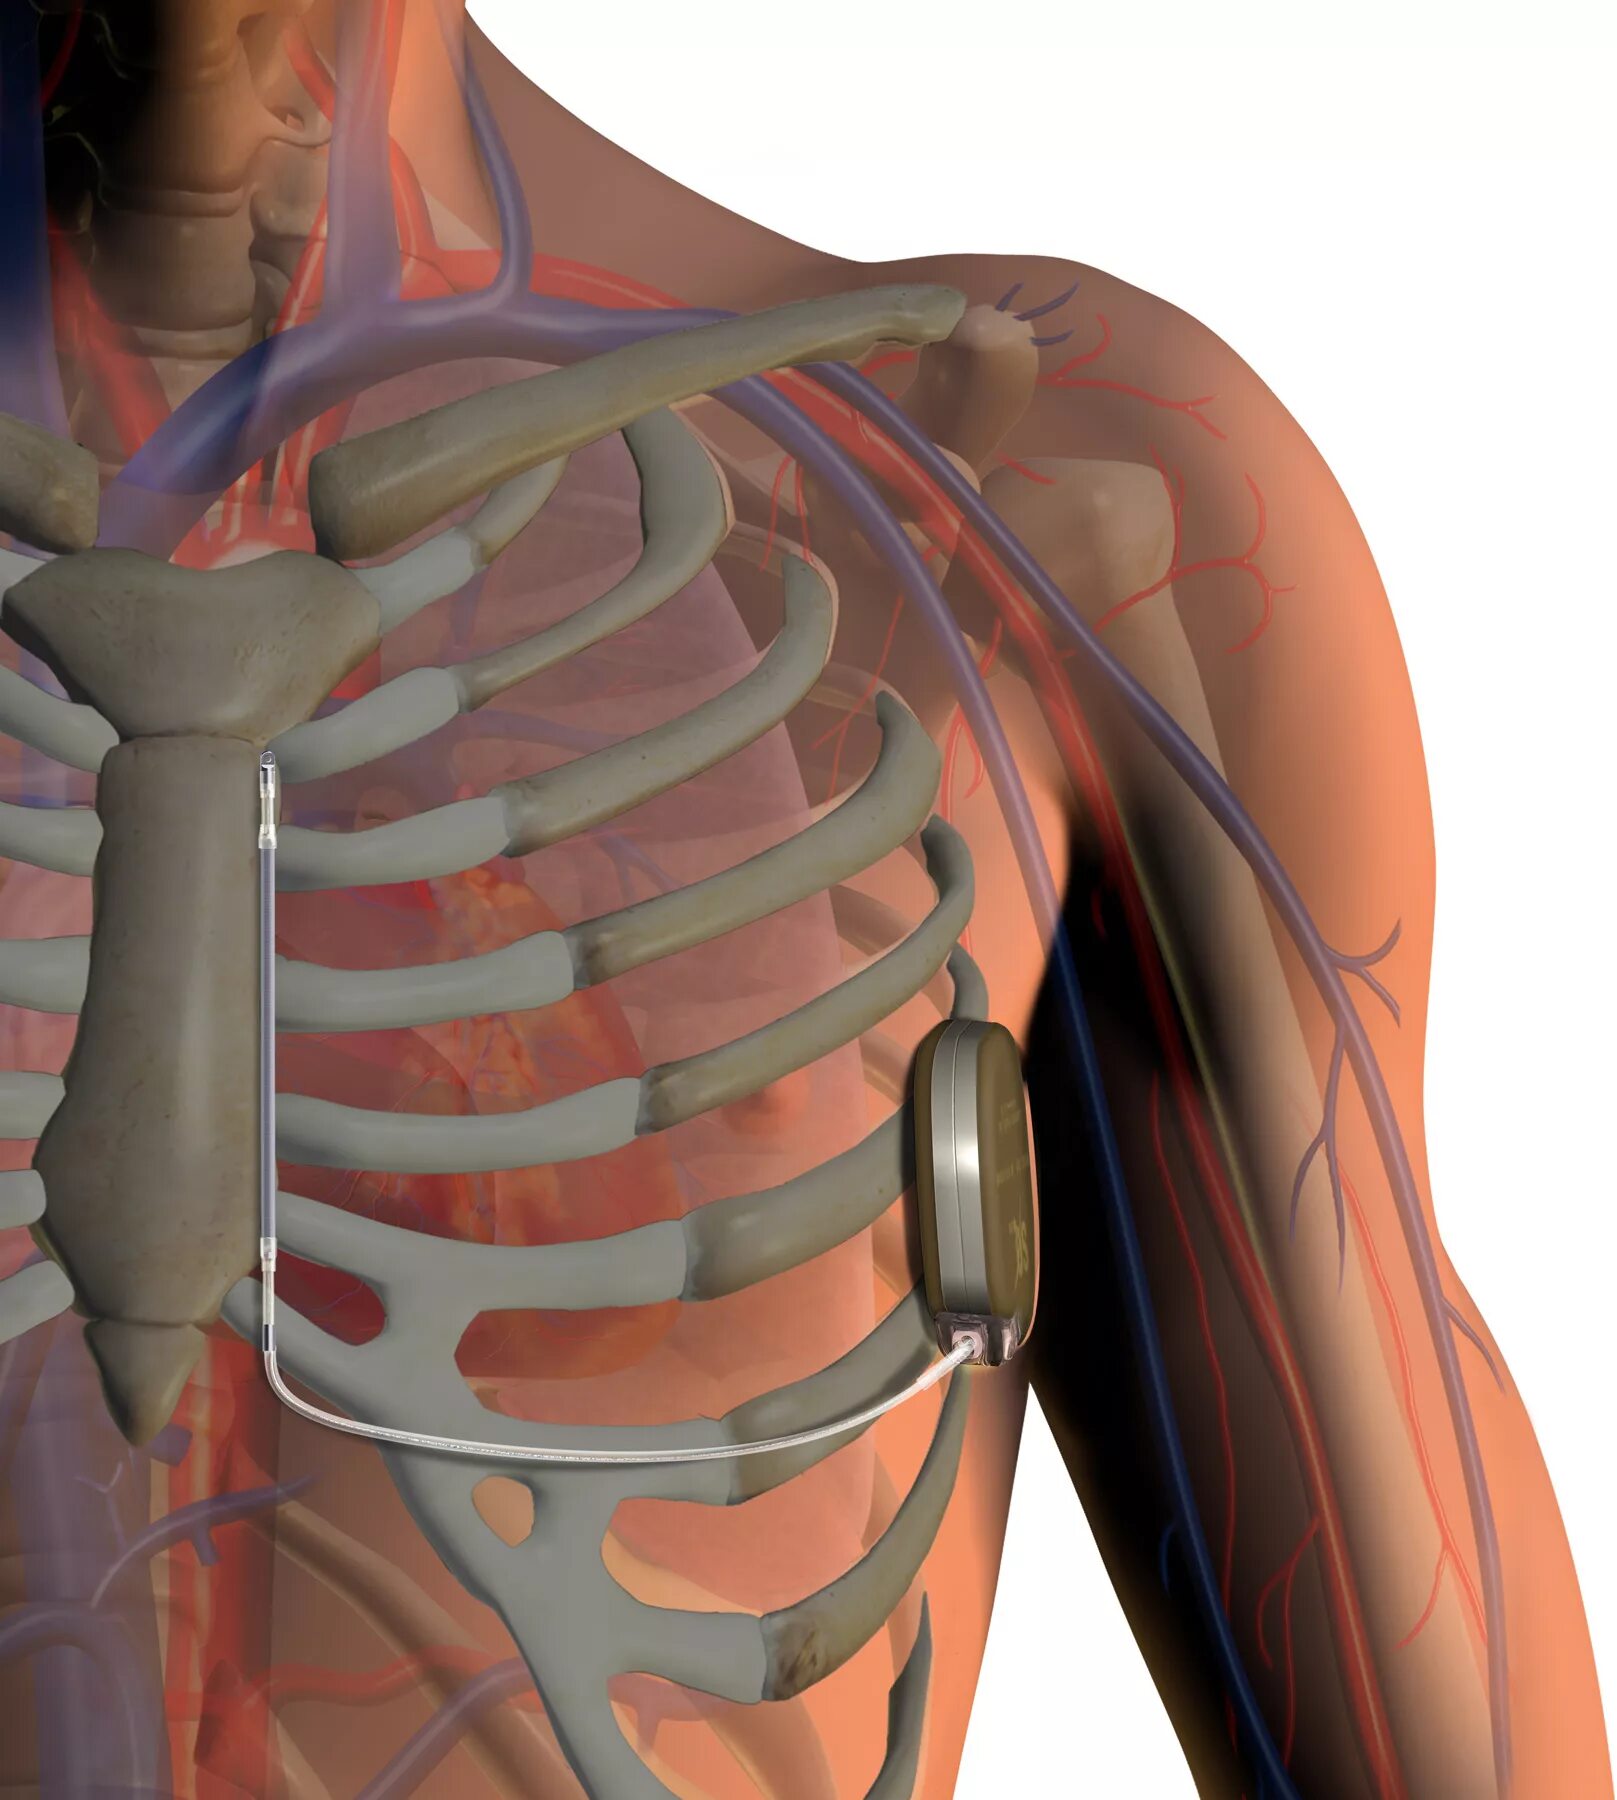

Инфаркт после операции шунтирования